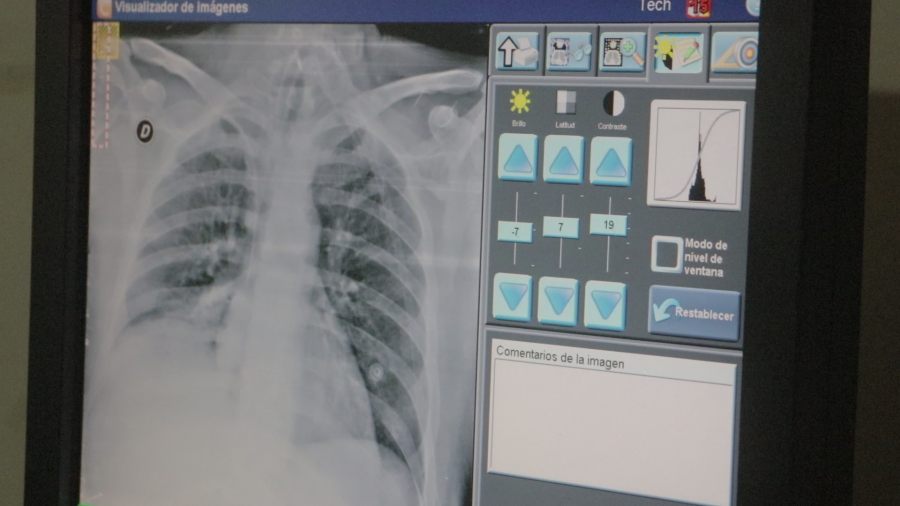

Es un programa de intervención multidisciplinaria para pacientes con enfermedades respiratorias crónicas. Participan neumonólogos, kinesiólogos, licenciados en salud mental, y, en ciertos casos, cardiólogos y nutricionistas.

La Dra. Susana Azcona, del Servicio de Neumonología del Hospital Escuela indicó que la jornada brindará información sobre el programa, su funcionamiento y los beneficios para pacientes con EPOC, enfermedades intersticiales, EPI, hipertensión pulmonar y secuelas pulmonares.

“Se discutirán síntomas como disnea y limitaciones en la vida diaria, y se destacará la importancia de la rehabilitación para mejorar la calidad de vida”, dijo la profesional.